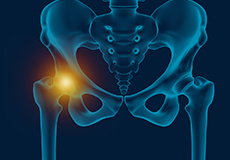

Greater Trochanteric Pain Syndrome

GTPS, also called trochanteric bursitis, is a localized painful condition affecting your outer thigh and hip area where the pain is typically confined to only the outer side of the femur at the edge of the hip.

Trochanteric Bursa Injections

A trochanteric bursa injection is a minimally invasive procedure in which medicine is injected directly into the trochanteric bursa in the hip joint using a thin needle and syringe to relieve pain and inflammation. The injection usually contains a combination of numbing medicine and cortisone (an anti-inflammatory agent). Trochanteric bursitis, also known as greater trochanteric bursitis or hip bursitis, is the main indication for a trochanteric bursa injection.